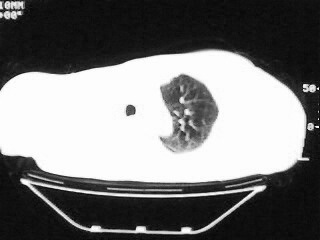

以下是引用随光逐影在2009-2-10 0:07:00的发言:[br]1)右肺放射性肺炎并节段性肺不张?请结合相关病史。2)右侧胸膜肥厚、粘连。3)心包膜增厚(或心包少量积液)。